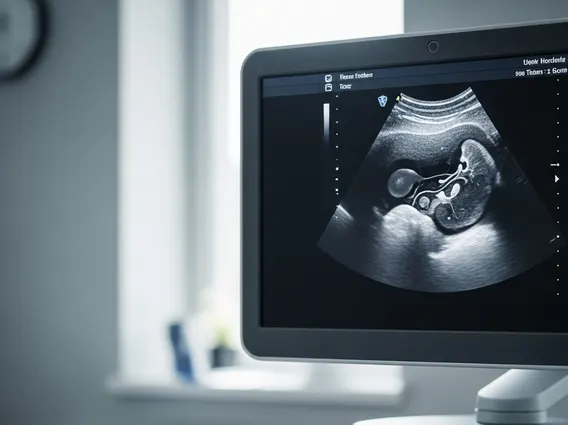

Abdominal Ultrasound is a diagnostic imaging method that employs sound waves to produce pictures of the internal organs located in the abdomen. This non-invasive technique uses a small transducer (probe) that emits sound waves and detects the echoes as they bounce off structures such as the liver, gallbladder, spleen, pancreas, kidneys, and major blood vessels. The echoes are then converted into real-time images displayed on a monitor, allowing healthcare professionals to assess the size, shape, and condition of these organs. The procedure is painless and does not involve radiation, making it a safe option for various patients, including pregnant women.

When considering an abdominal ultrasound procedure explained, it typically involves the patient lying on an examination table while a sonographer applies a special gel to the abdomen. This gel helps the transducer make full contact with the skin and eliminates air pockets that could interfere with the sound waves. The sonographer then moves the transducer across the skin, capturing images from different angles. Patients might be asked to hold their breath or change positions to improve image quality. The entire process usually takes between 30 to 60 minutes, and the images are reviewed by a radiologist who then prepares a report for the referring physician.